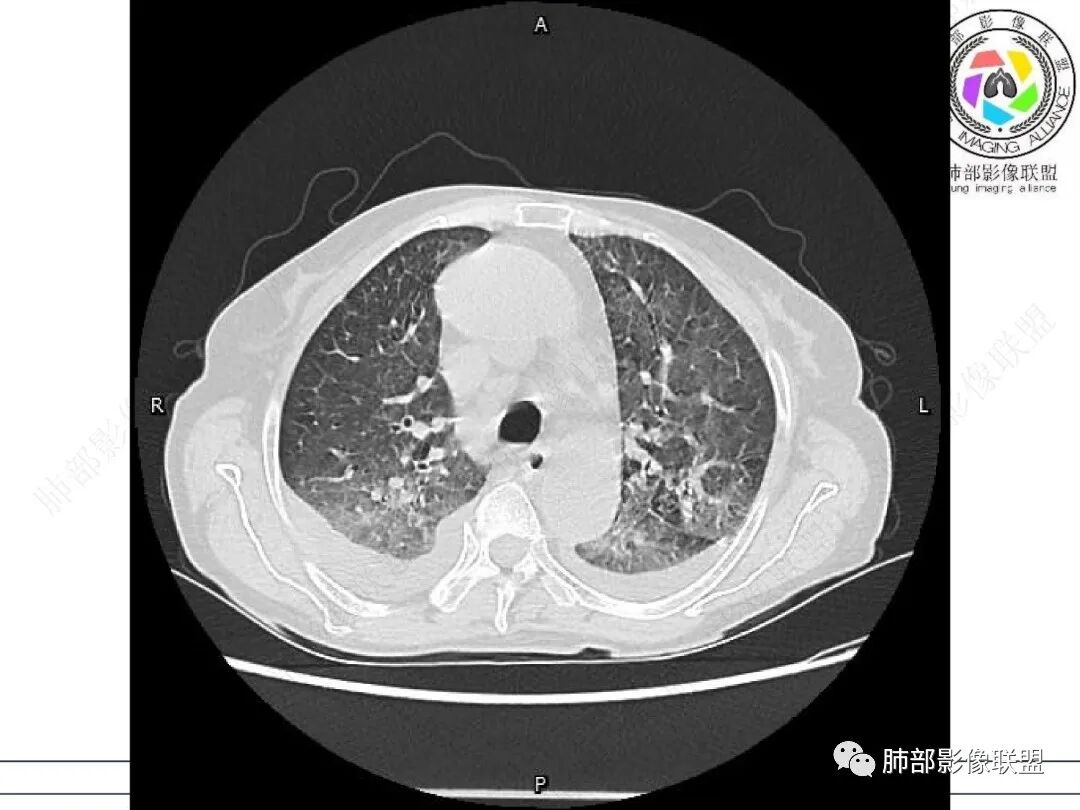

女,71,外阴疼痛2周,发热1周。类风关、高血压、高血糖、卵巢囊肿、肠粘连、胆囊结石等病史及相关药物治疗史。胸部CT:两肺弥漫磨玻璃,血管束增粗,两下肺后肋膈角多发蜂窝,对称分布,双侧胸腔少量积液,纵隔窗心脏大血管影明显增宽。考虑混合性病变,CTD-ILD,并肺水肿?并PJP?。

①影像表现复杂:较弥漫间质性改变,对称磨玻璃密度为主,小叶间隔增厚,有一定重力分布趋势,未见明显纤维化,气囊及蜂窝位于肺边缘,未见典型“月弓征”。心脏影增大,双侧胸腔积液。

这即可见于间质性肺病,也可见于真菌感染(如PJP)、病毒感染,类风湿,以及肺水肿等等。

一般而言,如存在磨玻璃密度影浑浊,有重力分布趋势,肺表面蜂窝影,胸腔积液等等,并不常见于单纯PJP,除非其他因素叠加。

患者存在肺水肿应当是合理的解释。其他旁证还有,心脏影增大,肾小球滤过率降低,双侧胸腔积液等等……